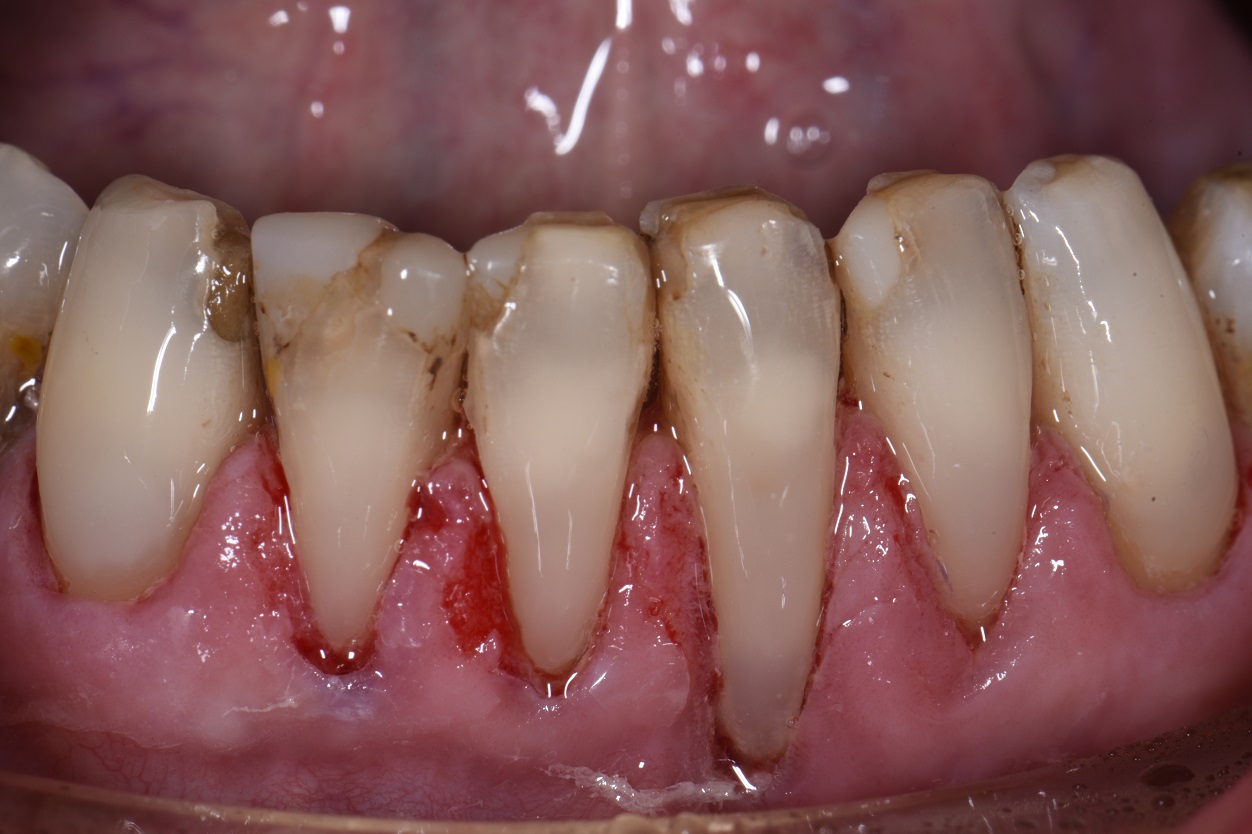

Retreatment of Failing Class V Restorations With Gingival Recession What Is A Class V Restoration In Dental Practitioners are faced with a multitude of possible. The class v with subgingival. Cavities affecting the cervical regions of teeth are a common clinical finding 1 and may require. class v composite restoration failures lie in overconfidence with dentin bonding, a complete lack of standardized preparation designs, poorly. — class iii, iv, and v direct composite restorations are. What Is A Class V Restoration In Dental.